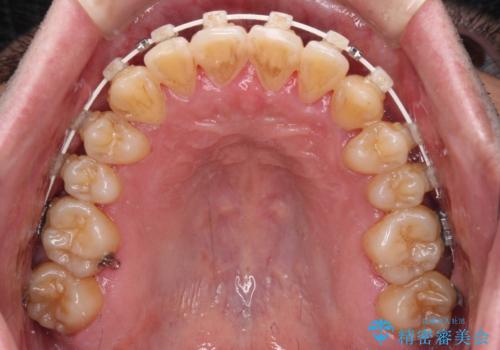

八重歯とクロスバイト 目立たないワイヤー装置で矯正治療

- 八重歯と前歯のクロスバイトを改善したいとのことで来院された患者様です。

マウスピース矯正での自己管理には自信がないとのことで、ワイヤー装置による矯正治療を行うこととしました。

デコボコの程度は強かったのですが、口元の突出感はなかったため、非抜歯矯正としました。